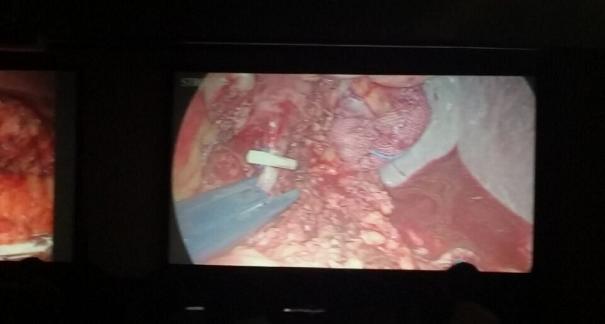

2015年10月23-25日,河北省醫(yī)學(xué)會(huì)肝膽外科學(xué)術(shù)年會(huì)在河北省石家莊市頤園賓館隆重召開(kāi)。本次學(xué)術(shù)會(huì)議河北省醫(yī)學(xué)會(huì)特邀了北京301總院的胡明根教授、天津第一中心醫(yī)院的張雅敏教授、山西醫(yī)大醫(yī)院的趙浩亮、河北醫(yī)科大學(xué)第二醫(yī)院劉建華教授等國(guó)內(nèi)知名專(zhuān)家參會(huì)。參加會(huì)議的醫(yī)院達(dá)100余家,近300名肝膽外科的臨床專(zhuān)家和一線(xiàn)醫(yī)生們親臨會(huì)場(chǎng),在此進(jìn)行廣泛的學(xué)術(shù)交流。25號(hào)全天會(huì)議安排了五臺(tái)手術(shù)視頻演示,全體參會(huì)人員進(jìn)行觀(guān)摩,并實(shí)時(shí)提問(wèn),進(jìn)行手術(shù)交流。演示手術(shù)包括腹腔鏡胰、十二指腸切除術(shù)、腹腔鏡左、右半肝切除術(shù)、腹腔鏡門(mén)脈高壓癥的治療、兩鏡或三鏡聯(lián)合膽石癥的治療、開(kāi)腹胰、十二指腸切除術(shù)、手術(shù)演示中多次使用了我公司產(chǎn)品速豐(可吸收止血結(jié)扎夾),產(chǎn)品使用滿(mǎn)意度受到專(zhuān)家們的一致好評(píng)。